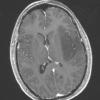

NEOPLASMS (GLIAL)

Astrocytoma, IDH-mutant, WHO Grade 2 (6)